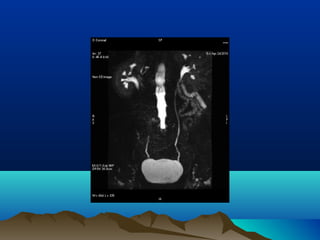

DIAGNOSISDIAGNOSIS

โ€ข IVP โ€“ OBSOLETE

โ€ข MR UROGRAPHY

โ€ข TO DIFFERENTIATE PHYSIOLOGICAL FROM CALCULUS

โ€ข HYDRONEPHROSIS

โ€ข DOUBLE KINK SIGN โ€“ SPINDLE SHAPED PELVIC URETER